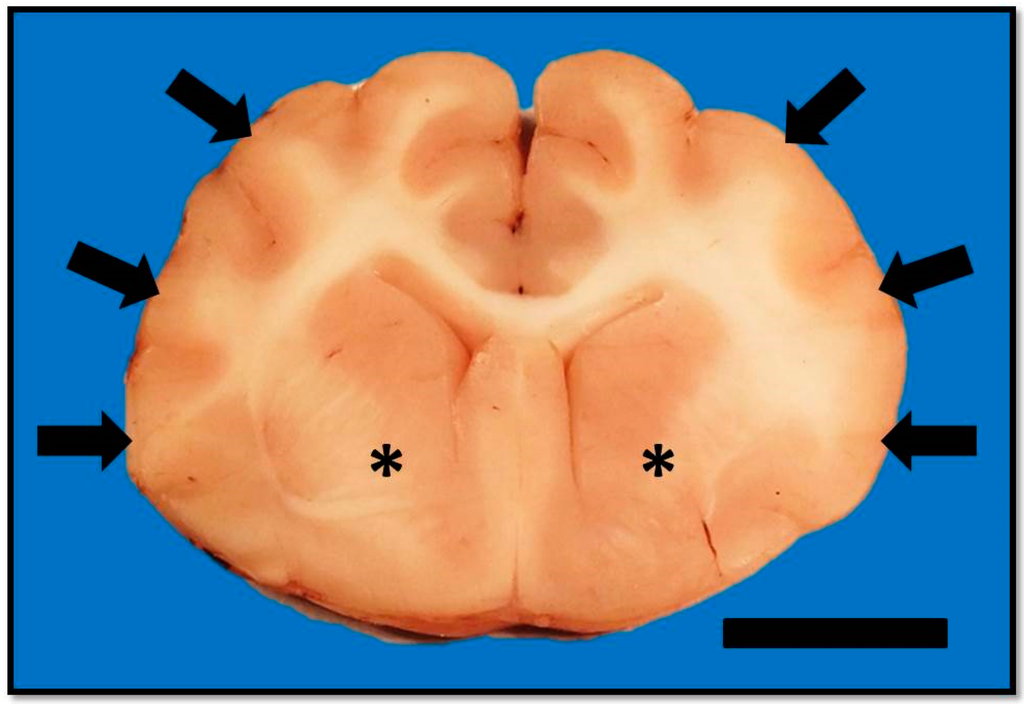

On histopathologic examination, ventral grey and white matter of the cerebrum (including the olfactory nuclei, olfactory tracts, corpus striatum, lateral septal nuclei, medial septal nuclei, thalamic nuclei and hippocampus), cerebellum, and brain stem (predominantly affecting the olivary nuclei) were bilaterally but asymmetrically infiltrated and expanded by dense sheets of neoplastic cells that merged gradually into the adjacent parenchyma, resulting in indistinct margins between normal and abnormal tissue (Figure 4a). The neoplastic cells had indistinct cytoplasm, ovoid to elongated or curved hyperchromatic nuclei, and indistinct nucleoli (Figure 4b). Anisokaryosis was mild and there was one mitotic figure per 10 400× fields. Multifocally, the neoplastic cells formed secondary structures of Scherer, including foci of subpial spread (predominantly along the ventral aspect of the brainstem; Figure 5a), subependymal aggregates (Figure 5b) with multifocal extension into and expansion of the leptomeninges, and minimal perineuronal satellitosis (Figure 5c). The neoplastic cell population was negative for Olig2, GFAP, Iba1, CD3, and Pax5. Scattered among these cells were variable numbers of GFAP-positive astrocytes, Olig2-positive oligodendrocytes, and Iba1-positive microglia. All examined sections of spinal cord were histologically unremarkable. Based on the cellular morphology, immunolabeling characteristics, and anatomical location, a diagnosis of gliomatosis cerebri was made.

Figure 4. Transverse section of the brain at the level of the interthalamic adhesion. (a) Subgross photomicrograph showing loss of general anatomical detail within the thalamic nucleus and internal capsule due to a poorly delineated neoplastic mass (asterisk). Neoplastic cells also obscure the sylvian gyrus, hippocampus, and intervening parenchyma (arrows). HE. Bar = 5 mm. (b) Inset of (a). The neoplastic cells have indistinct cytoplasm, ovoid to elongated or curved hyperchromatic nuclei, and indistinct nucleoli (arrows). HE. Bar = 20 μm.